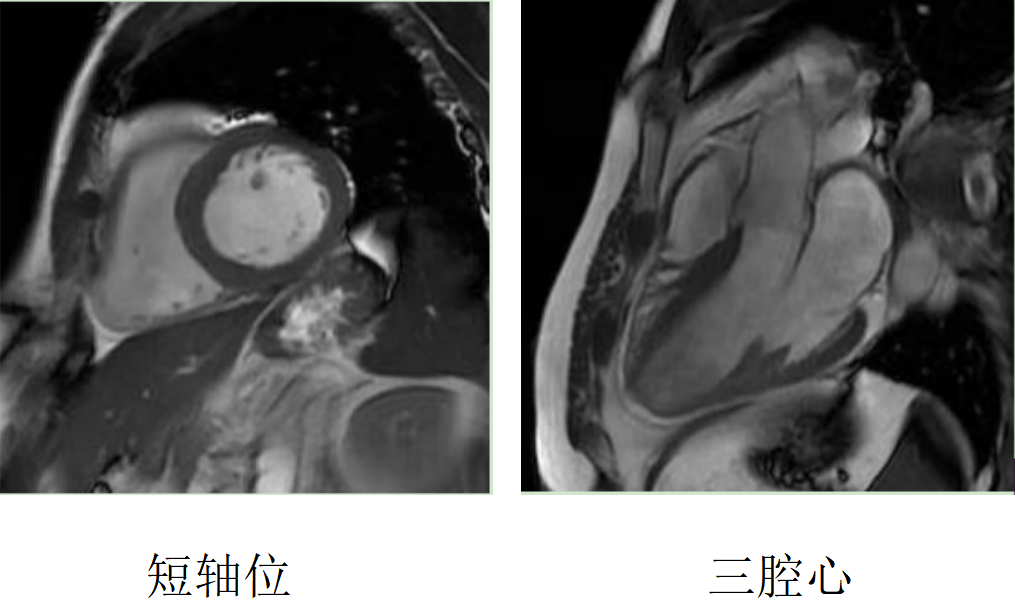

心臟磁共振被稱為心臟“一站式”檢查,通過多參數(shù)成像能夠?qū)π呐K的結(jié)構(gòu)、功能、室壁運動、心臟瓣膜、心肌灌注和活性進行“一站式”評估。主要通過電影序列(短軸、兩腔心、四腔心、三腔心)、T2WI序列、首過灌注序列以及延遲強化序列對心臟進行綜合成像。

擴張型心肌病

肥厚型心肌病,舒張末期心尖形似“黑桃A征”